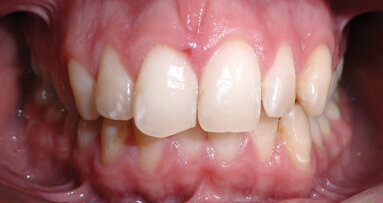

Un uomo di 21 anni si presenta con un importante disturbo dovuto a una ricaduta di un trattamento ortodontico effettuato durante l’adolescenza. Ha ...